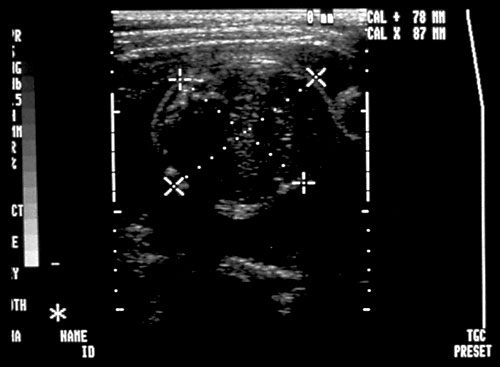

- Amniotic Fluid Index (AFI)

- Measure of vertical measurement (centimeters) of deepest fluid pocket in each of four abdominal quadrants

- Saggital plane

- Measurement line should exclude umbilical cord/fetal parts

Single Fluid Pocket >= 2 cm.

- Must be demonstrable in at least two anatomic planes